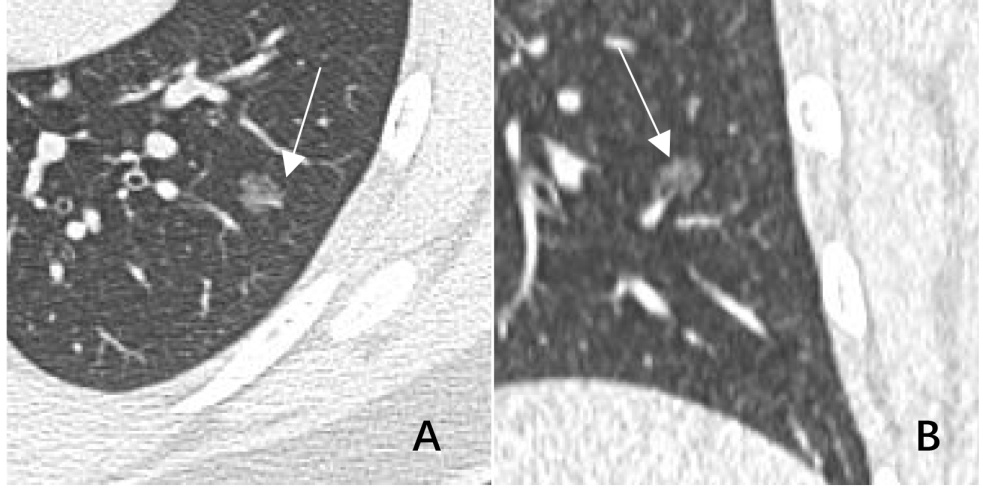

2) 右肺上叶直径6 mm约pGGN (见图2),无明显分叶毛刺,AI判定为MIA,恶性概率78%,后经病理证实为AAH (A,轴位,箭头;B,冠状位,箭头)。

Figure 2. Typical images of AI misdiagnosis

2. AI误诊典型图像